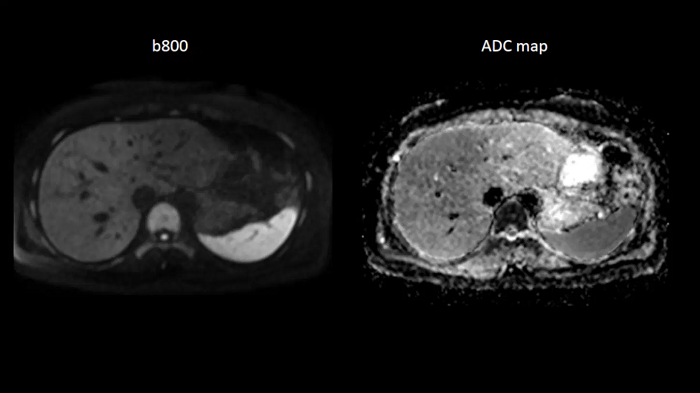

Abdomen

Body diffusion imaging

For all-inclusive abdominal MR capabilities, outstanding quality diffusion imaging.

MAC-ID: 7aaaa0165. Image Credit: Siemens Healthineers